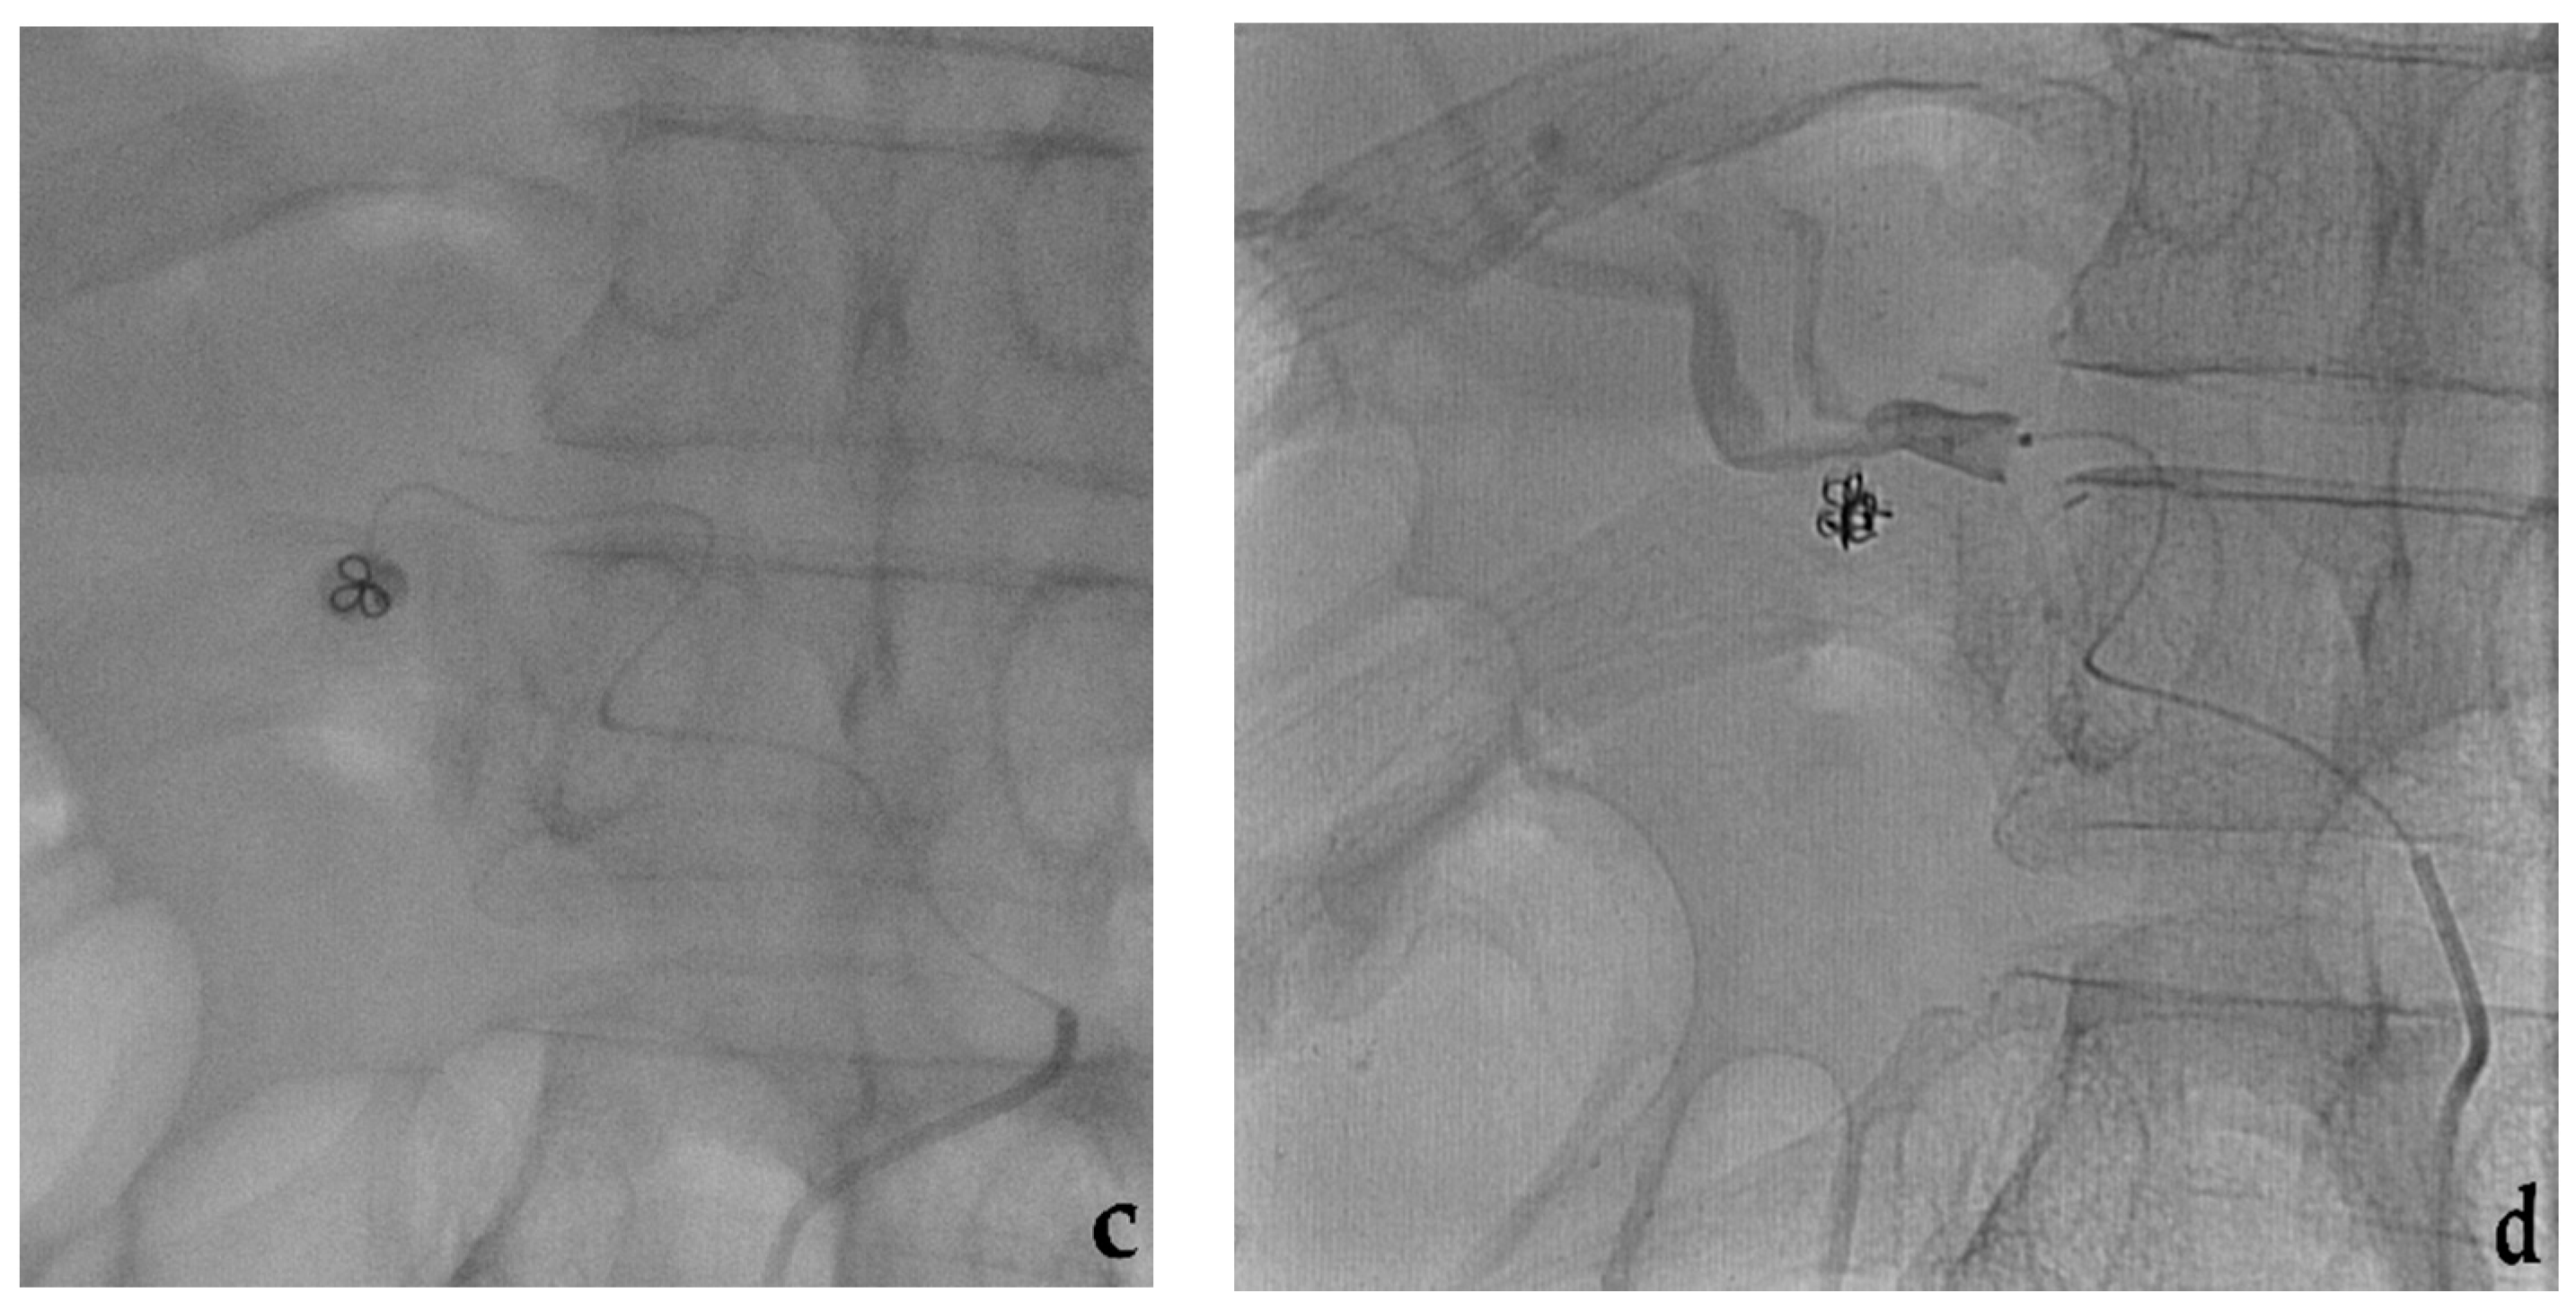

- Venturini, M.; Marra, P.; Colombo, M.; Panzeri, M.; Gusmini, S.; Sallemi, C.; Salvioni, M.; Lanza, C.; Agostini, G.; Balzano, G.; et al. Endovascular repair of 40 visceral artery aneurysms and pseudoaneurysms with the Viabahn Stent-Graft: Technical aspects, clinical outcome and mid-term patency. Cardiovasc. Interv. Radiol. 2018, 41, 385–397. [Google Scholar] [CrossRef]

- Venturini, M.; Marra, P.; Colombo, M.; Alparone, M.; Agostini, G.; Bertoglio, L.; Sallemi, C.; Salvioni, M.; Gusmini, S.; Balzano, G.; et al. Endovascular treatment of visceral artery aneurysms and pseudoaneurysms in 100 Patients: Covered stenting vs transcatheter embolization. J. Endovasc. Ther. 2017, 24, 709–717. [Google Scholar] [CrossRef] [PubMed]